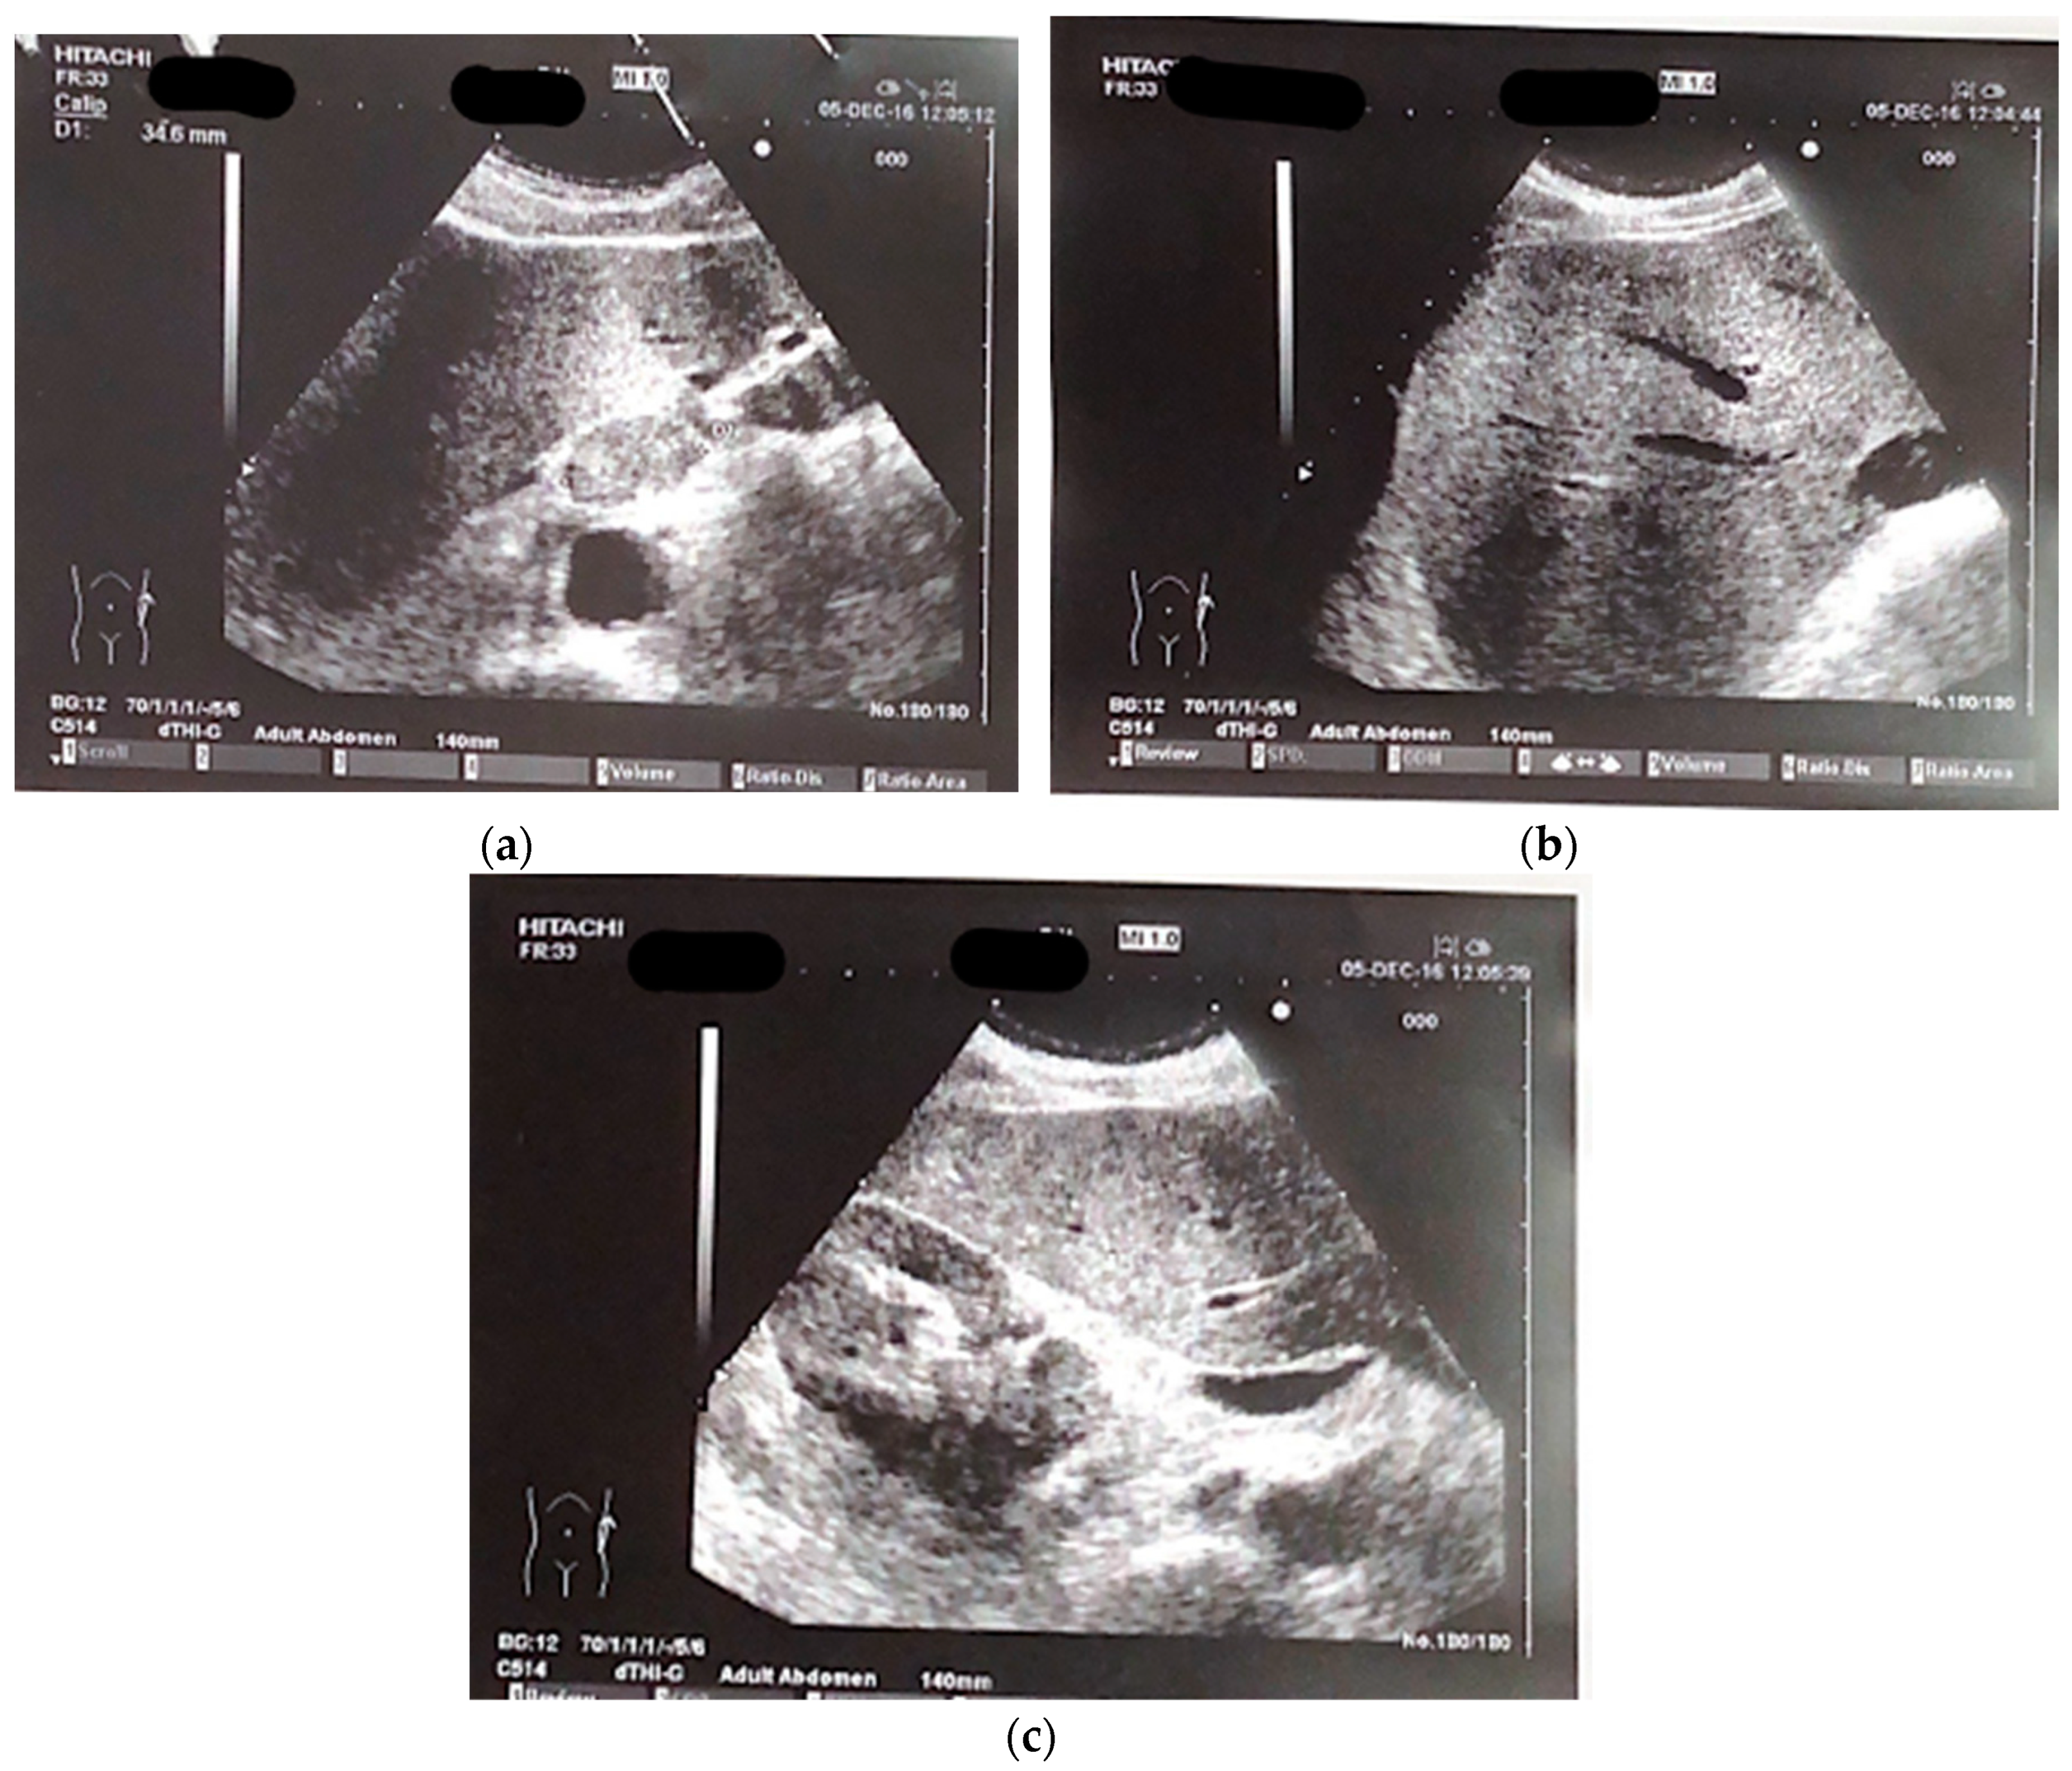

A 65-year-old male patient presented at our hospital in 2016 with worsening non-productive night cough but no dyspnea. He had a history of hypertension and a recent diagnosis of gastroesophageal reflux. A former smoker who quit 10 years ago, he had not experienced weight loss in recent months. An abdominal ultrasound revealed an area near the hepatic hilum with lobulated contours, roughly oval, displaying iso-hypoechogenic echo structure, with a maximum diameter of 43 mm, indicating the presence of malignant lymph nodes (Figure 1a–c).

Figure 1. a-c: The abdomen ultrasound images of perihepatic lymphadenopathy.